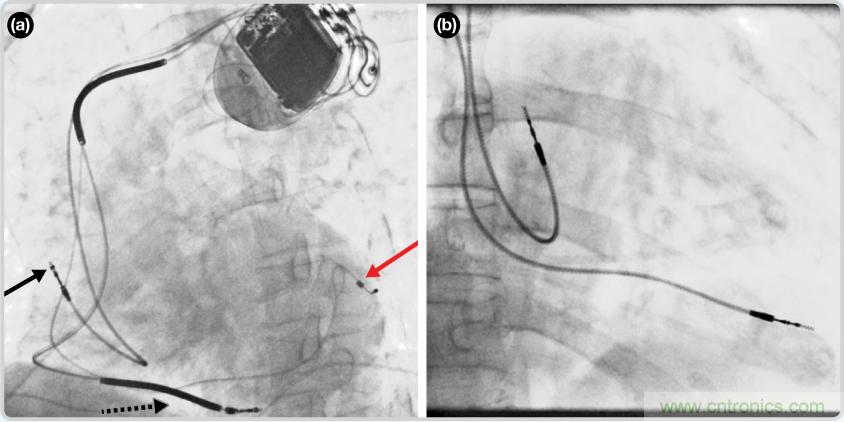

CRT器件在圖4(a)中的透視圖像中可以看見。醫(yī)師就是利用這種影像來放置導(dǎo)聯(lián)線的。對于非專業(yè)人士來說,這種影像是很難解讀的??梢钥吹叫呐K淡淡的輪廓——這是搏動(dòng)中的心臟的靜態(tài)視圖。起搏器位于右心房上,心臟頂點(diǎn)指向右下方。在這個(gè)典型的導(dǎo)聯(lián)線放置實(shí)例中,黑色箭頭指向右心房導(dǎo)聯(lián)線。虛線黑色箭頭指向右心室導(dǎo)聯(lián)線。紅色箭頭標(biāo)示的導(dǎo)聯(lián)線只能看到一部分,這是左心室導(dǎo)聯(lián)線(紅箭頭指向電極尖端)。圖4(b)展示的是雙腔起搏器的典型導(dǎo)聯(lián)線放置透視圖像。右心房導(dǎo)聯(lián)線指向上方,置于右心房中。右心室導(dǎo)聯(lián)線則位于右心室頂部。

圖4. 起搏器導(dǎo)聯(lián)線放置的透視圖像3 (a). 單腔起搏器;(b).雙腔起搏器